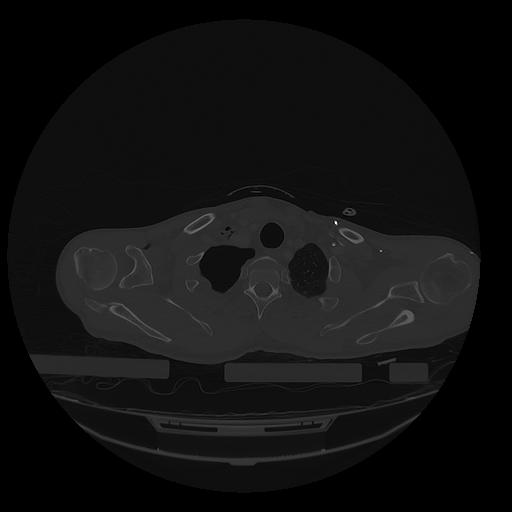

31 PULMON,CE,Vol,1.0,PULMON,,